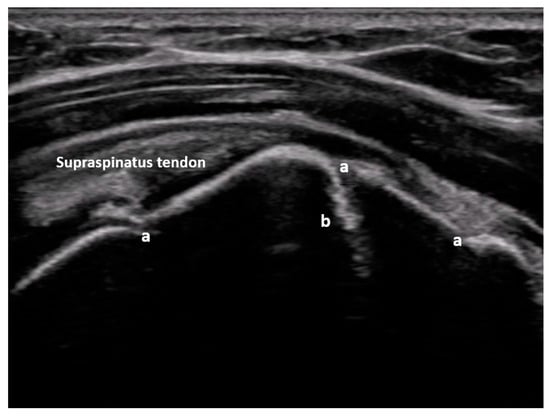

Figure 4.

Non-displaced major tuberosity fracture: lateral sagittal view at the level of the major tuberosity with corticalis interruptions (a) and chimney sign (b). Image courtesy of J. Osterwalder.